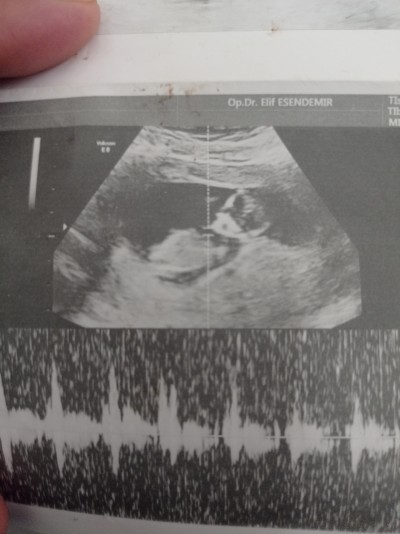

selam aleyküm arkadaşlar hayırlı geceler hayırlı sahurlar  dediğim gibi sadece merak maksat sohbet şimdiden teşekkürler hakkınızı helal edin kızlar burda 12 haftalık ❤️

Kiz mi erkekmi çünkü bu büyük ihtimalle kiz

İkiside var canım çok şükür d iki farklı Dr erkeğe benziyor dedi yarın özele gitcem bakalım artık hayırlısı olsun inşallah rabbim olmayana nasip etsin inşallah ❤️

Erkek geçti içimden :)

KIZ

Bana erkek gibi geldi

Erkeğe benzettim sanki :)